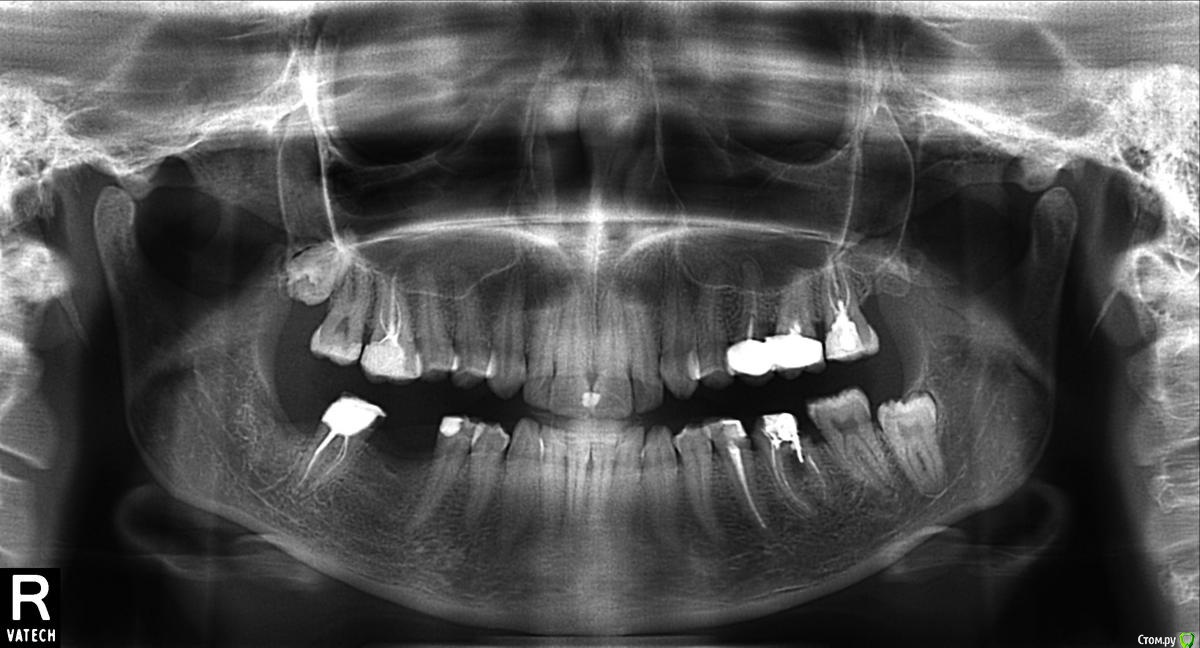

Jonatan Опубликовано 24 февраля, 2015 Поделиться Опубликовано 24 февраля, 2015 Здравствуйте!Прошу прокомментировать ситуацию,лечусь долго, а проблемы только растут.Началось с того, что сделали перфорацию в резорциненном 6-м нижнем зубе (он пока стоит, но под удаление).И было три зуба под депульпацию-восстановление, плюс необходимость закрывать отсутствие нижних 6-к и удалять 8-ки.Была удалена 8-ка справа внизу с большими проблемами после (3 недели кетанова и боль в десне еще месяца два после),7-ка справа внизу рядом с ней - пролечен пульпит, каналы, и вышли на этап восстановления (от идеи импланта я отказалась из-за осложнений после удаления, решилась на мост). Сразу после установки однокоренной культевой вкладки на цемент в 7-ку начались проблемы:1. 3-5 дней после зуб остро реагировал на горячее и холодное (разламывающая сильная боль в зубе и всей челюсти).2. Боль локализовалась в участке десны, прилегающей к 7-ке со стороны удаленной 8-ки, и уже 2 месяца десну дерет-мозжит,при касании зубочисткой как удар током, никакие полоскания-примочки не спасают.Врач ничего не говорит по поводу. Подточил цемент, трижды отсылал "неделю пополощите", потом сказал сделать ОПТГ. Еще один протезист посмотрел, увидел, что в зоне беспокойства обнажен металл вкладки и контактирует со слизистой.Также выразил сомнение по поводу качества прохождения каналов.Вопросы: насколько корректно ставить в 7-ку однокорневую симметричную вкладку, частая ли это практика, или это 100% косяк?Насколько серьезные проблемы в пролеченными корнями? Сам зуб не беспокоит, только десна в этом одном месте.Хочу определиться со стратегией и сделать мост у хорошего специалиста, которого также ищу теперь снова.7-ка слева вверху пролечена со штифтом и пломбой, с тех пор болит при накусывании (боль асимметричная - при боковом давлении не больно, а при давлении на жевательную поверхность - болит, боль сильная при начале жевания и постепенно ослабевает в процессе) чуть слабее, чем сразу после лечения, но чувствительно, жевать на зубе могу не все и через день, на погоду возникает ощущение выпирания и пульсации. Вопрос: какие погрешности в лечении можно предположить по снимку и что делать?Спасибо! Ссылка на комментарий

SDC Опубликовано 27 февраля, 2015 Поделиться Опубликовано 27 февраля, 2015 И никто из специалистов не прокомментирует ситуацию? Свербеж в нижней правой 7-ке замучил, что делать, непонятно... С 47 зубом все ясно - обострение хр. периодонтита после фиксации вкладки.в 27 - похоже тоже самое.Требуется повторное эндолечение. Ссылка на комментарий